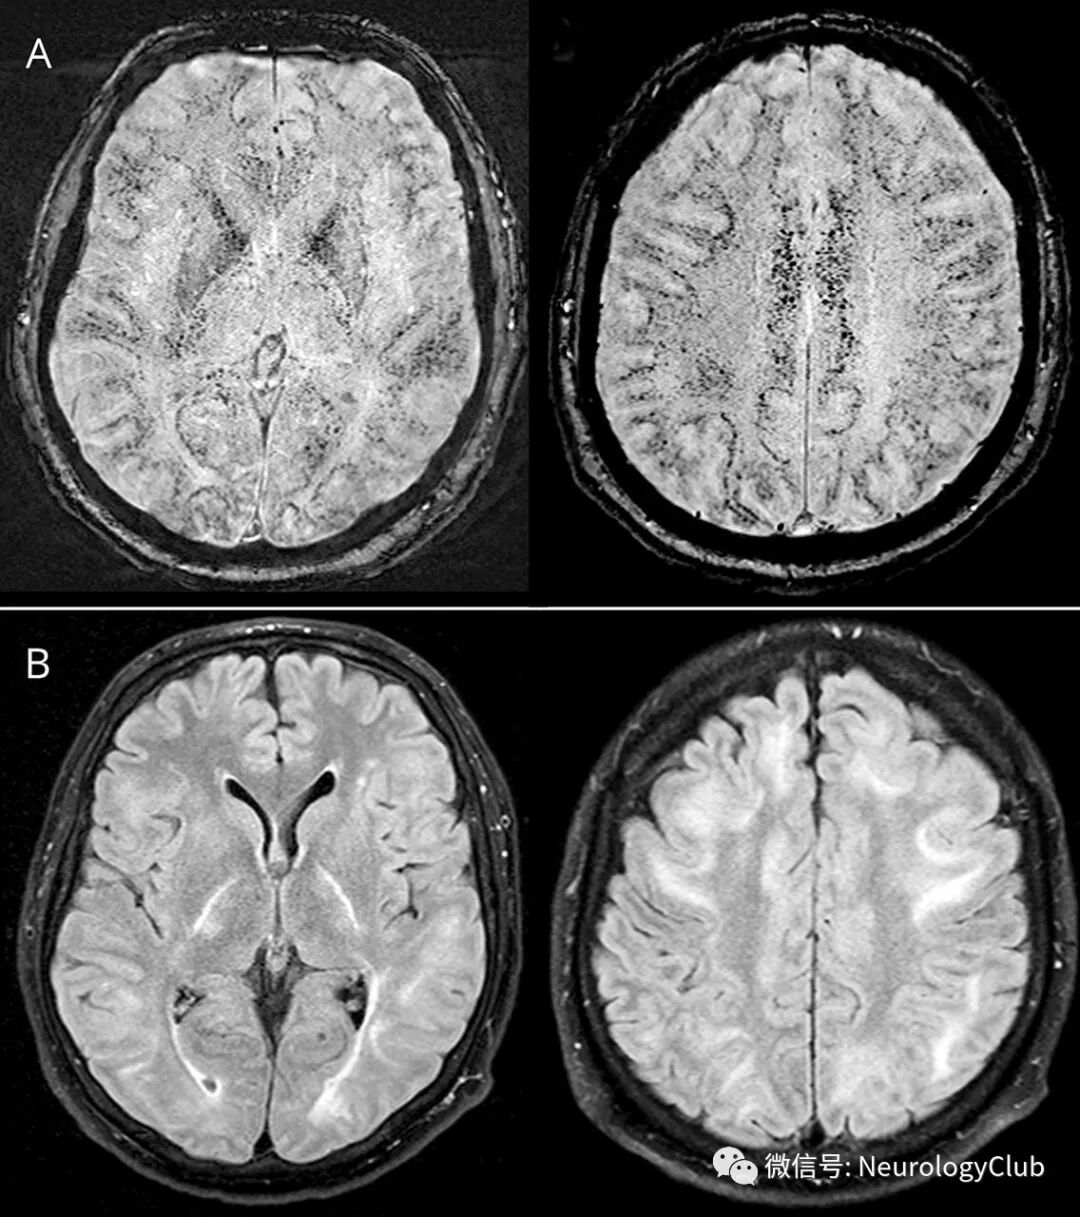

一名来自明尼苏达州的48岁男性在去南非狩猎前拒绝接受疟疾预防。在其返回后10天,出现身体疼痛,意识模糊,并逐渐进展为弛缓性无反应,急性肝肾功能衰竭,休克和血小板减少。MRI可见毛细血管受累所致大量微出血和水肿(图)。

(图:A-B:患者起病后2周的SWI和FLAIR可见皮质下白质大量微出血以及血管源性脑水肿;DWI[未放图]正常;1个月后复查MRI,脑水肿消退,但微出血没有减少)